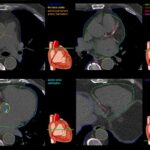

Non-contrast cardiac CT: much more than only calcium scoring!

This paper shows that we can extract a lot of information from plain cardiac CT. While calcium scoring is an obvious result, it is also possible to learn the amount of epicardial fat, an increasingly recognized prognostic factor of cardiac events, appearance of lungs,...